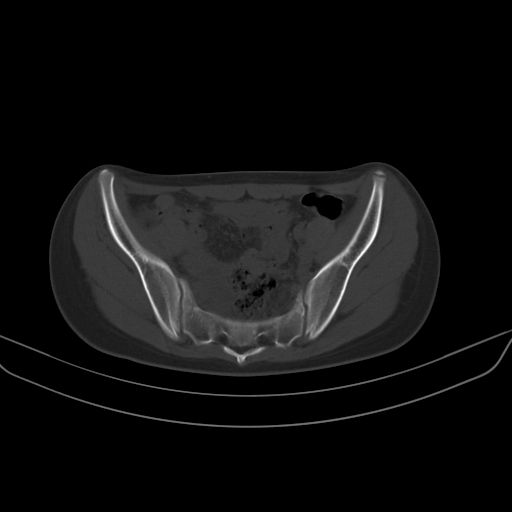

以下是引用zsl6918在2008-7-11 21:40:00的发言:[br]双侧骶髂关节骨质破坏以下三分之一为主,符合强直性脊柱炎表现

以下是引用zhangzhongshou在2008-7-11 21:41:00的发言:[br]患者是女性,hla-b27抗原(—),首先不太考虑强直性脊柱炎,建议查类风湿因子,骶髂关节改变考虑类风湿性关节炎可能性大,建议进一步检查。